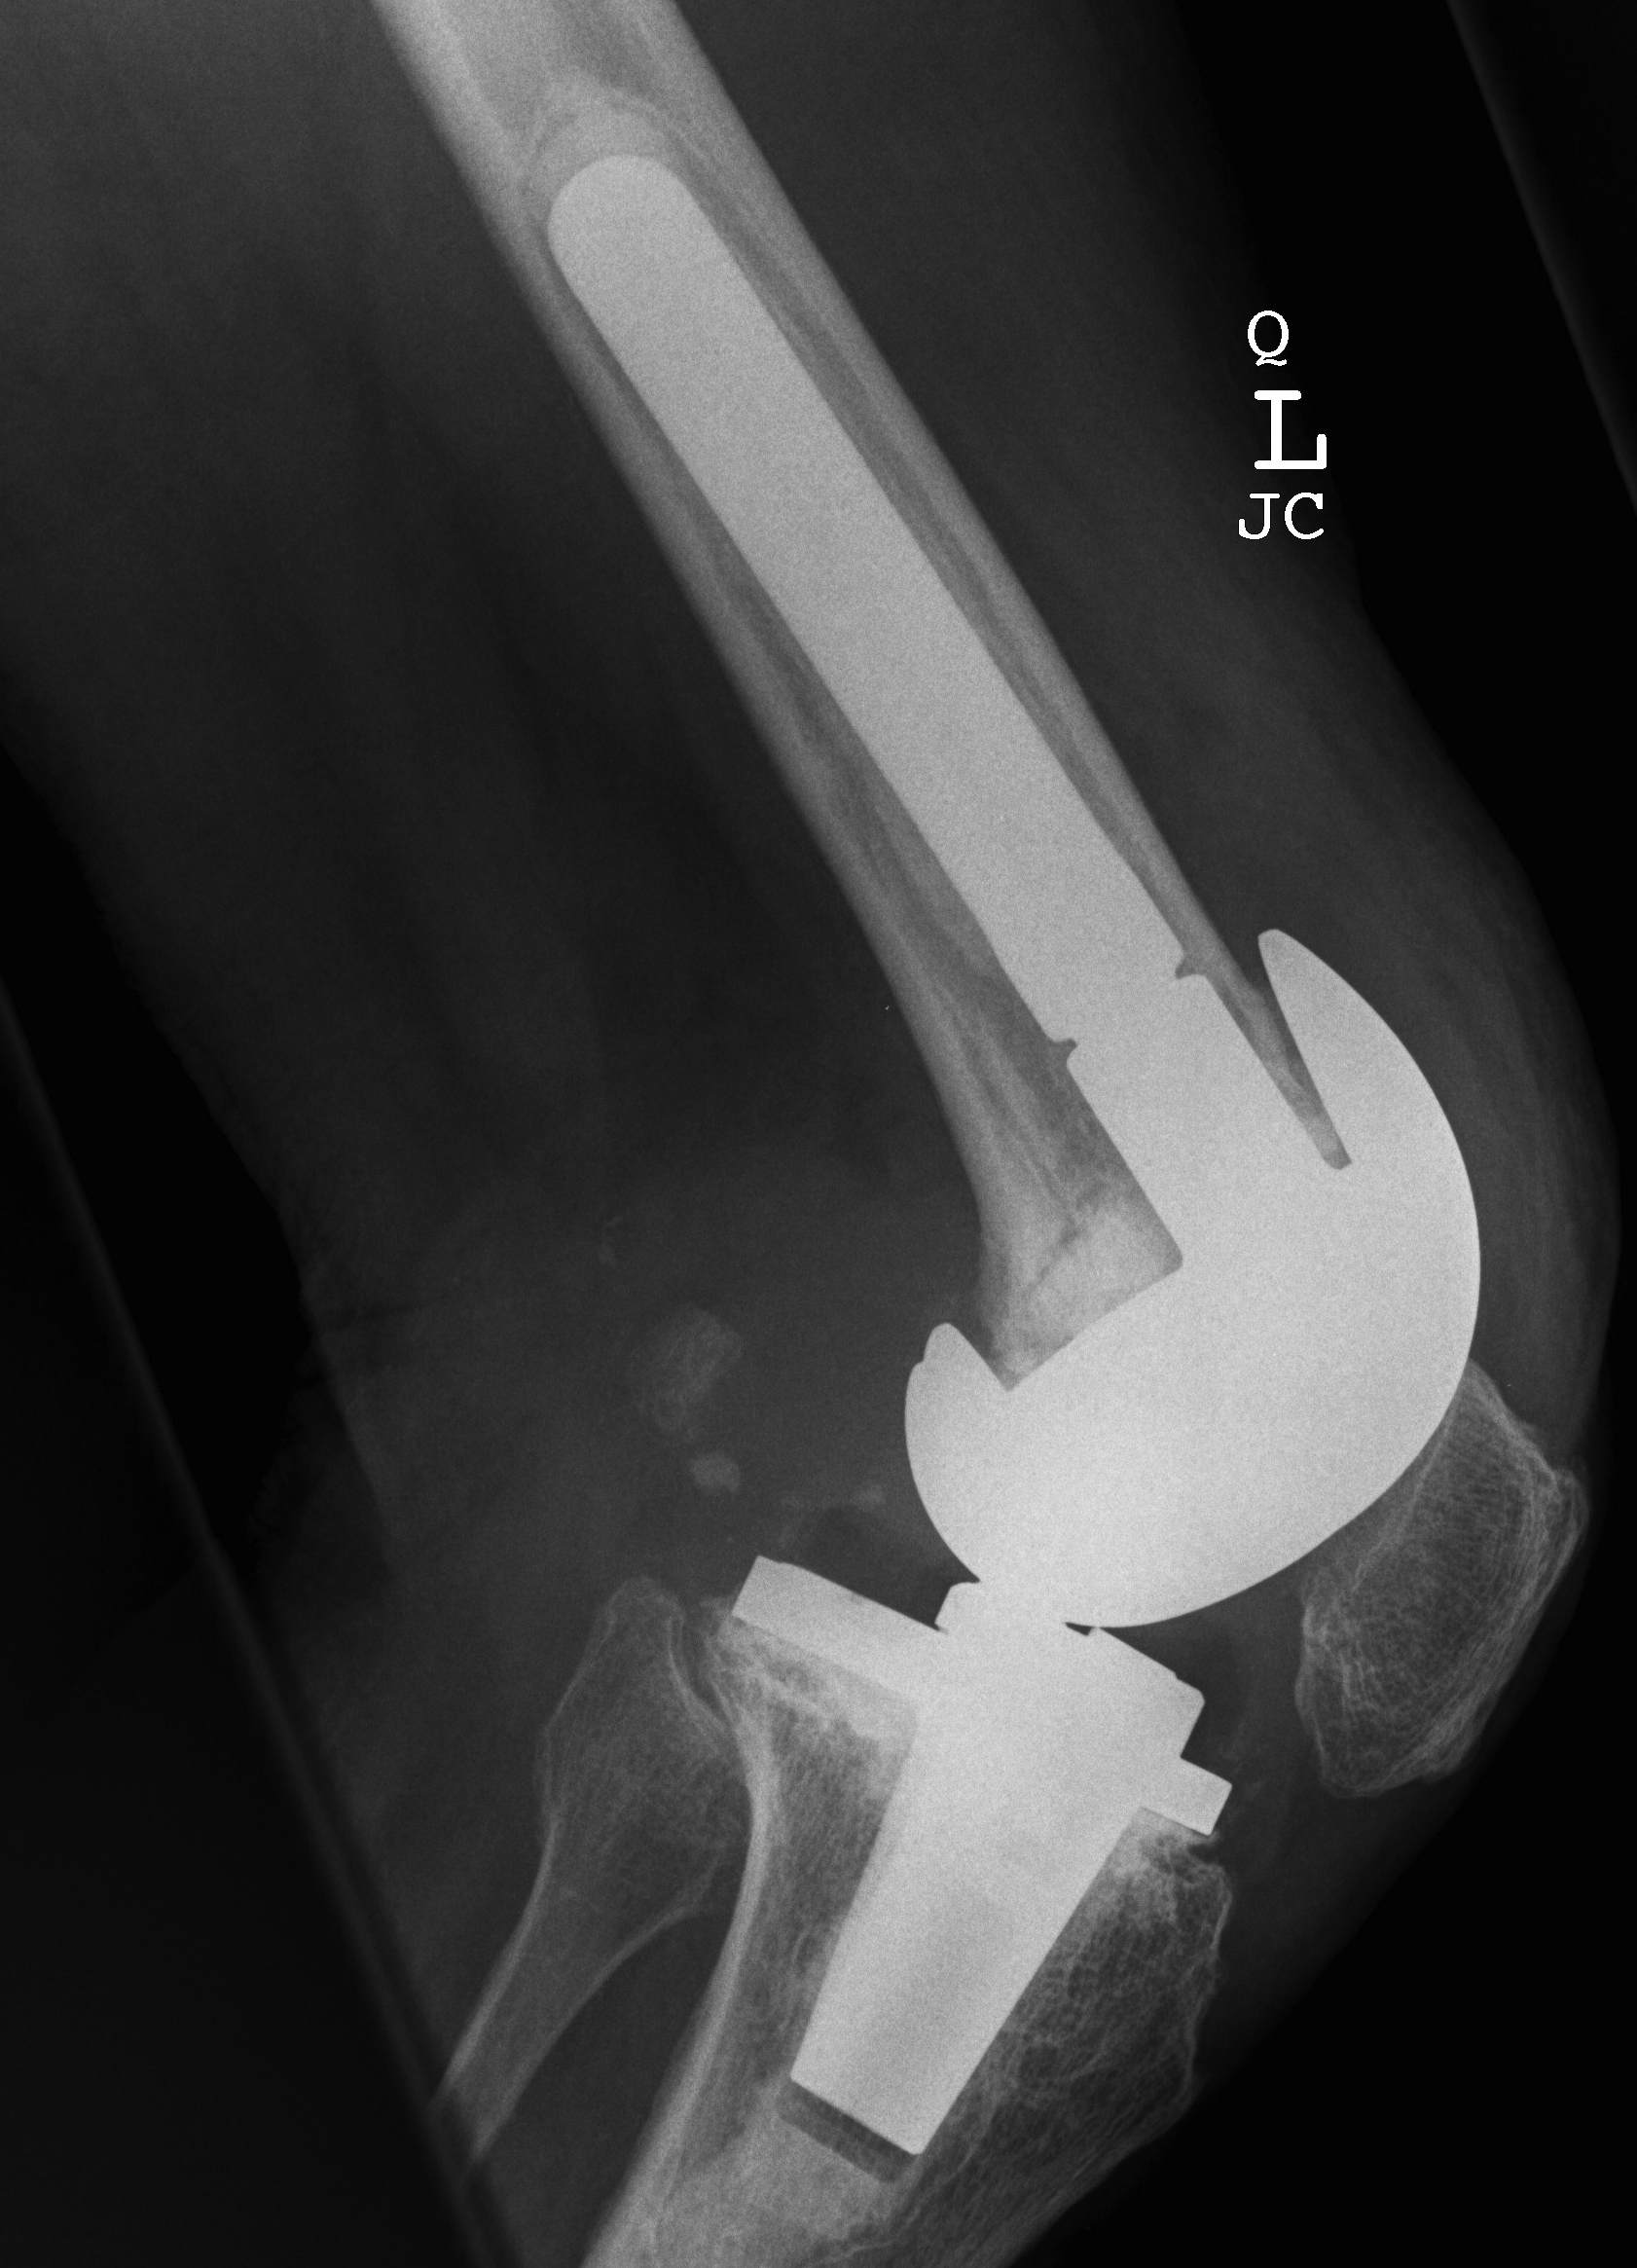

- 184 cemented revision TKR with press fit stems

- significant bone loss

10. Loosening